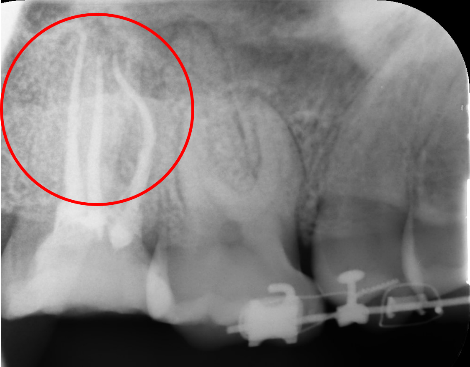

CASE02

感染根管治療20代 男性

初診時

-

治療後

主訴

歯茎が腫れて違和感がある。

治療の概要

歯髄壊死していたため、感染根管処置を行い、歯根充填をした。

リスクと副作用

コストがかかる。

- 治療費

- 176,000円

- 治療回数

- 2回